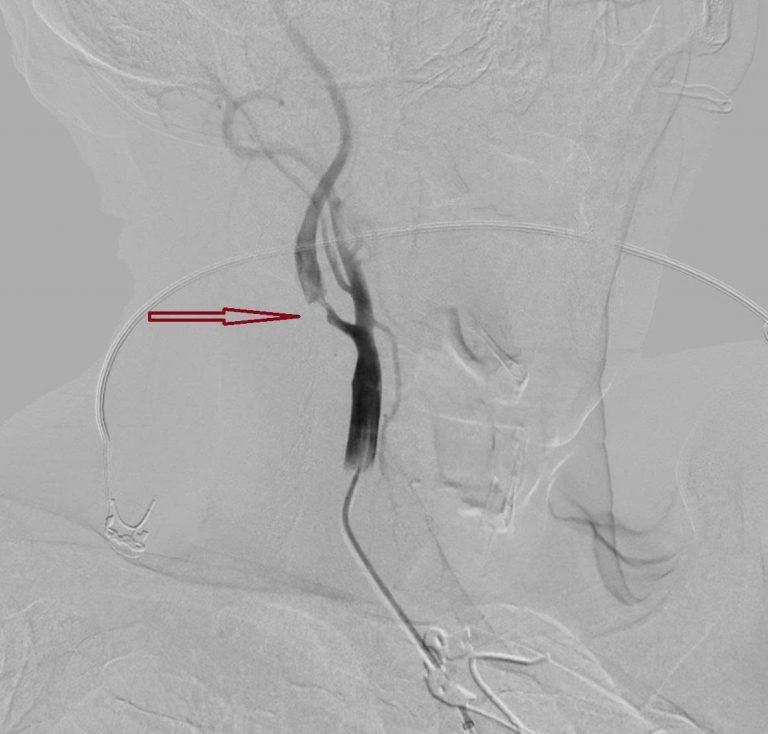

Hình DSA cho thấy hẹp nặng đoạn gốc động mạch cảnh trong ngoài sọ trước can thiệp của bệnh nhân đột quỵ. Ảnh: BVCC

Trước tình thế nguy cấp, từng giây phút đều quý giá để bảo vệ các tế bào não và tính mạng cho bệnh nhân, bác sĩ khoa Sọ não cột sống 2 cũng được huy động kịp thời. Song song đó, kết quả chụp CTA ghi nhận ông bị tắc động mạch não giữa M1 bên phải – một động mạch lớn, và hẹp nặng động mạch cảnh trong bên phải đoạn gốc.

Ca can thiệp đã diễn ra thành công dưới sự thực hiện của BS. Lục Đình Phương – Khoa Sọ não cột sống 2, bác sĩ đã tiến hành tái thông động mạch não giữa và nong bóng đoạn hẹp động mạch cảnh trong bên phải cho bệnh nhân bằng phương pháp gây tê.